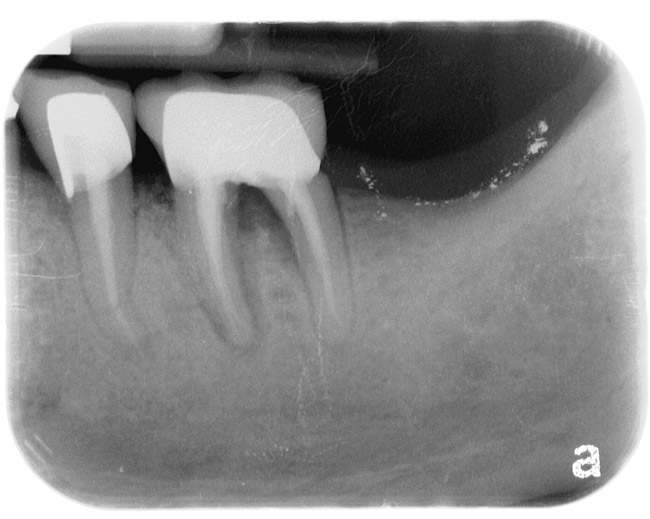

Figure 8  CLINICAL GUIDELINES  Horizontal defects can make guided tissue-regeneration attempts unpredictable.

Figure 8

Figure 9  CLINICAL GUIDELINES Narrow vertical defects respond more favorably to regeneration attempts. If periodontal surgery is attempted in the anterior region, the possibility of an esthetic compromise should always be considered regardless of defect morphology.

Figure 9